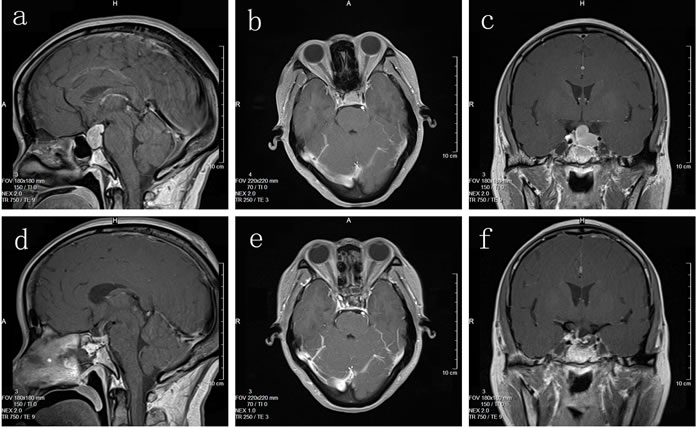

31 cases had total tumor excision; 9 cases had subtotal resection; 2 cases had partial resection. Postoperative symptoms improved to varying degrees: 18 of 22 patients with vision disorders and 19 of 25 patients with headaches improved significantly; of 15 patients with increased preoperative PRL, 11 regained normal levels; of 7 patients with elevated blood GH, 6 attained normal levels; of 3 patients with increased blood ACTH levels, normal levels were reestablished in 2; among the 4 mixed-type tumor patients, 3 regained normal hormone levels. Preoperative and postoperative MRI images are shown in Figure 2.

Figure 2: (a, b, c) Preoperative MRI imaging; (d, e, f) Postoperative MRI imaging.